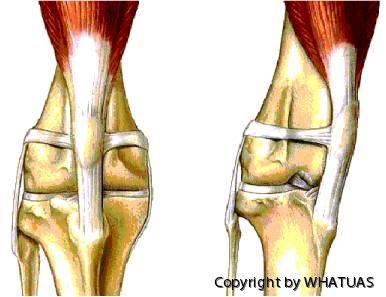

Nedan en bild på patellaluxation. Vänster normalt knä. Höger patellaluxation.